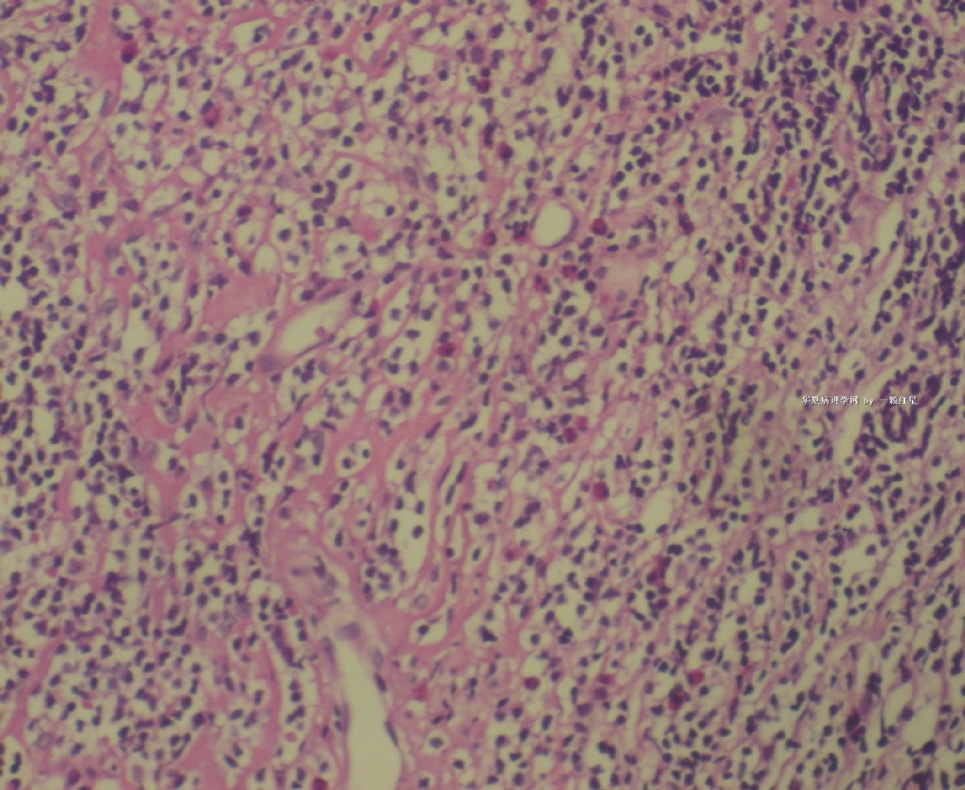

标本名称:  左前臂数个大小不等的皮下肿物。

既往有非何杰金淋巴瘤(滤泡性淋巴瘤)病史22个月。

• 左前臂数个大小不等的皮下肿物     淋巴瘤?图1

图1

病例不错。细胞胞浆透亮,间质血管丰富,图片不是很清晰,似乎有嗜酸粒细胞?

恶性,首先考虑T-NHL。IHC证实。

既往有NHL病史,图片不太清晰,细胞弥漫,胞浆透亮,首先考虑T细胞淋巴瘤。